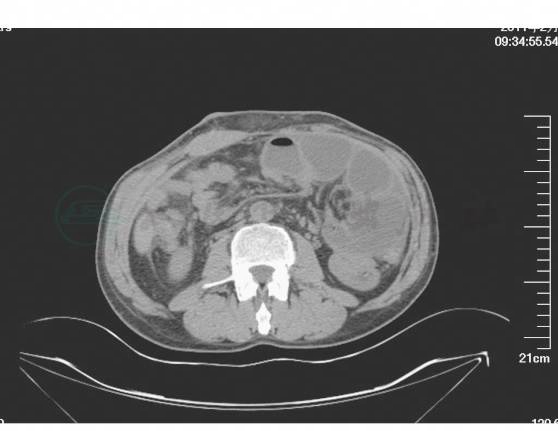

5.术后第10日复查腹部CT,显示近端小肠局限性明显扩张,扩张肠管周围有渗出,肠腔内大量积液,远端小肠及结肠则空虚,肝周可见少量积液(图4~图7)。此时肠梗阻原因考虑为“术后早期局限性炎性肠梗阻”。继续应用生长抑素保守治疗,加强肠外营养支持,热量供给35kcal/kg体重,并补充白蛋白纠正低蛋白血症,同时常规抗感染、抑酸治疗。

图4 术后第10日复查腹部CT图像(一)

图5 术后第10日复查腹部CT图像(二)

图6 术后第10日复查腹部CT图像(三)

图7 术后第10日复查腹部CT图像(四)